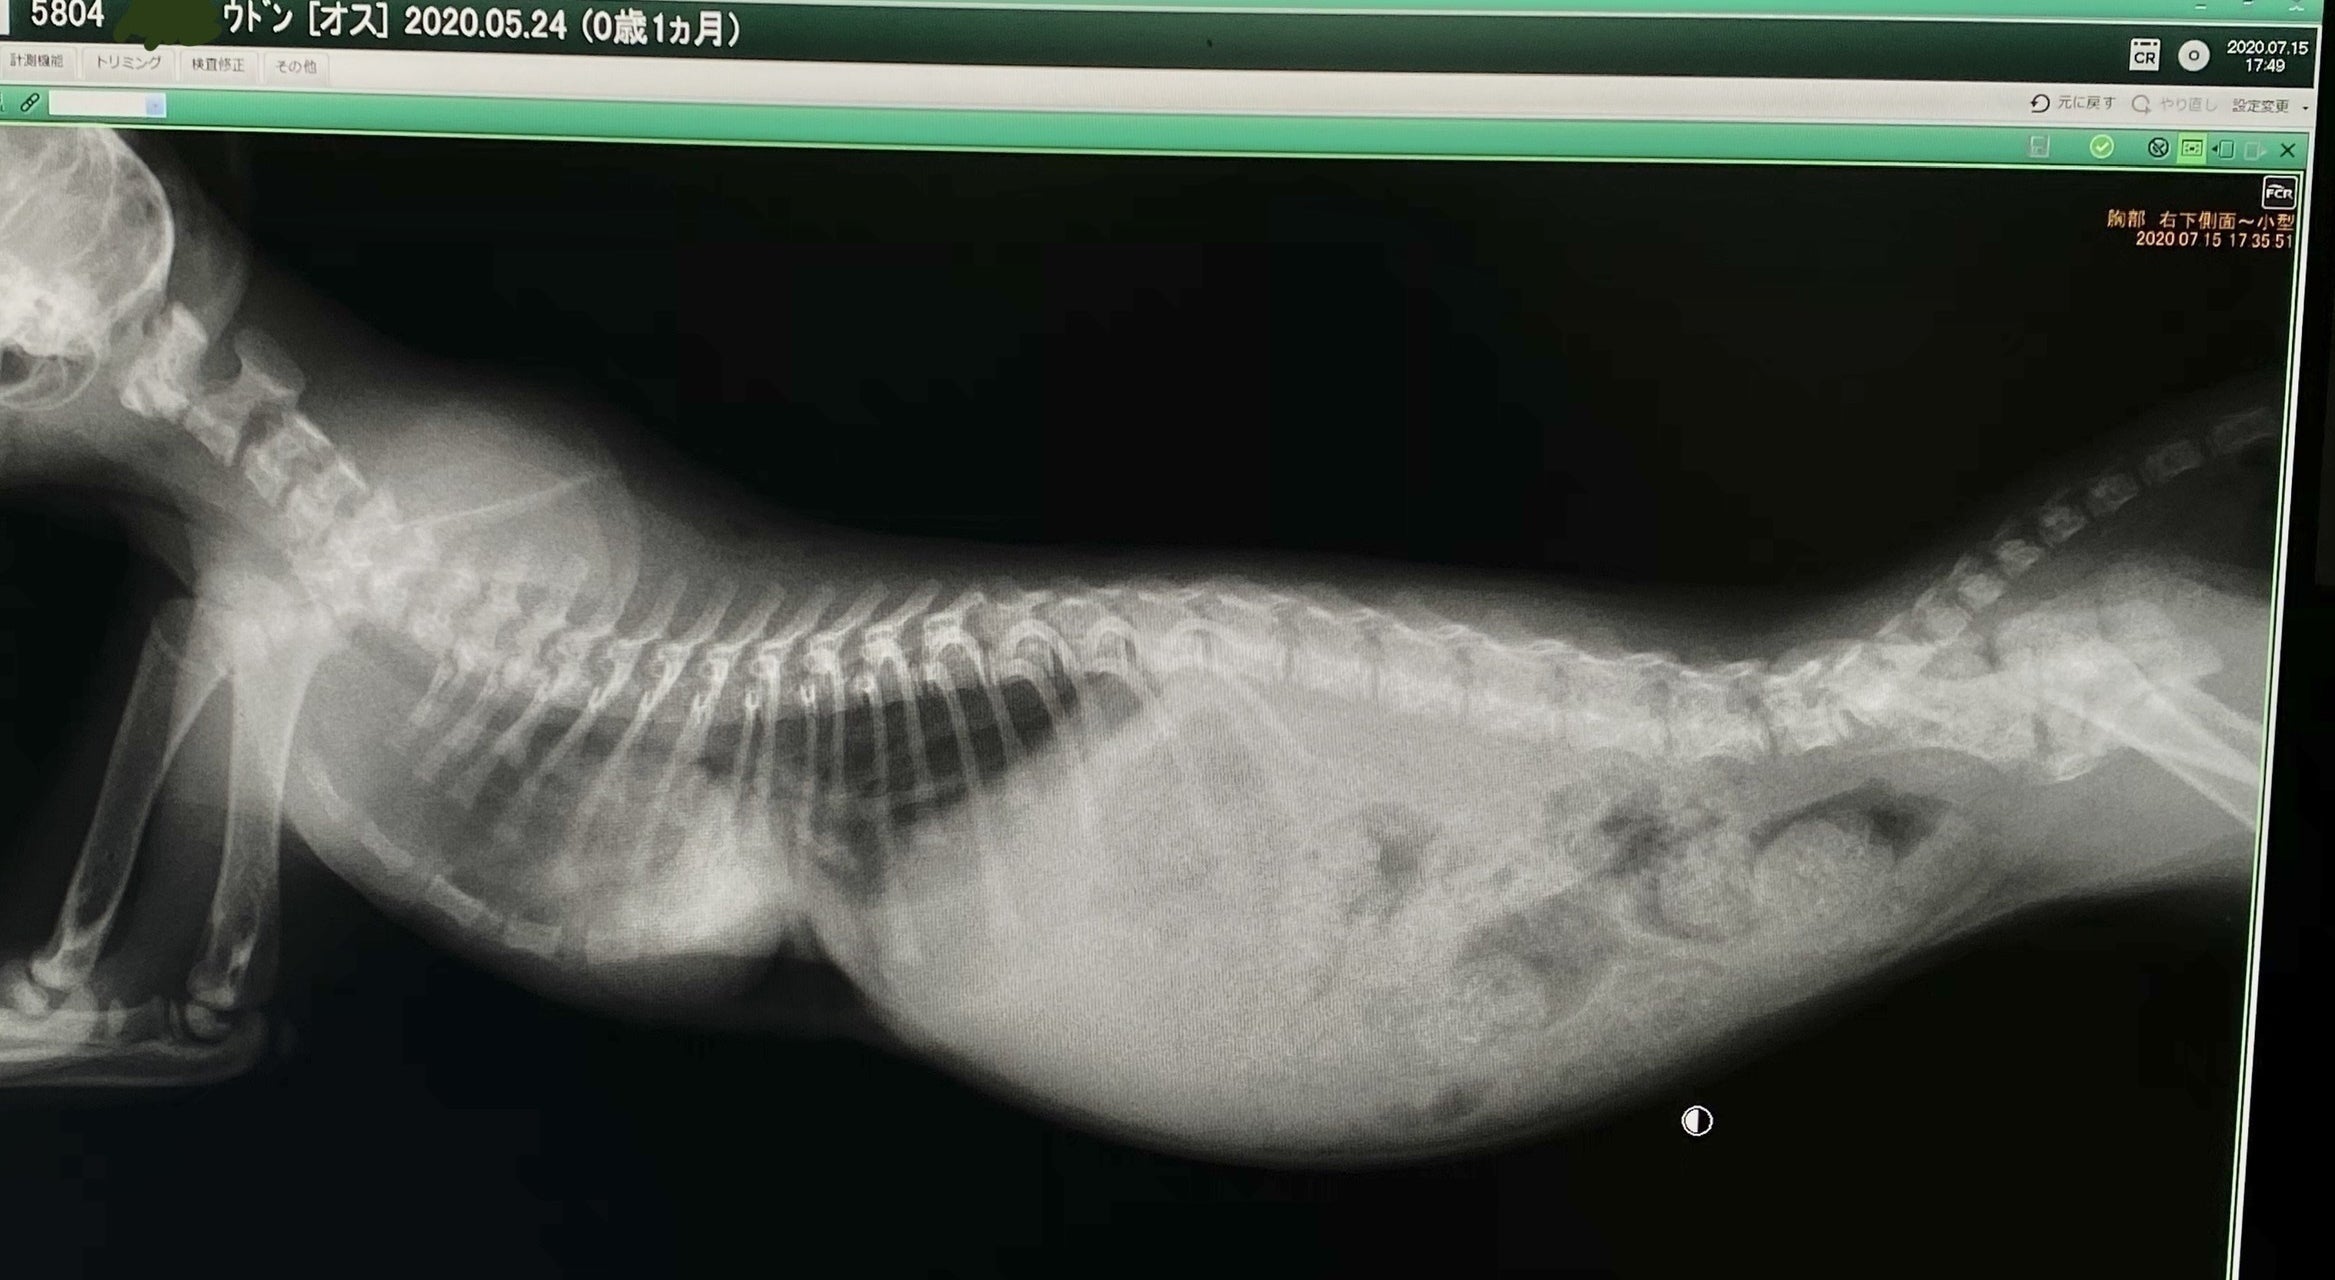

うどんちゃんが1ヶ月半になった先日、胸部の異常に気付き病院にかかりました。病院ではいわゆる奇形で重度の漏斗胸だと診断されました。

レントゲンを見た感じだと肋骨が内蔵(心臓)にくい込んでいる(通常じゃ有り得ないことなのでまだ未確定)可能性があり手術の難度も上がり、費用も通常よりもかなり高額になるとの事です。

見にくいですが肋骨の下に心臓(緑の丸の部分)があります。

肺も小さいので肺活量がかなり少なく、すぐにバテて動けなくなります…